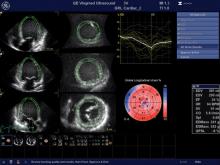

Cardio-oncology is an emerging field that combines the expertise of both cardiology and oncology to assess and treat cancer patients for the second leading cause of death among cancer survivors — cardiovascular disease brought on by their treatments. Specific types of chemotherapy and chest directed radiation therapy are known to cause cardiac dysfunction, mainly due to cardiotoxicity — the symptoms of which may not present until months or even years after cancer treatment.